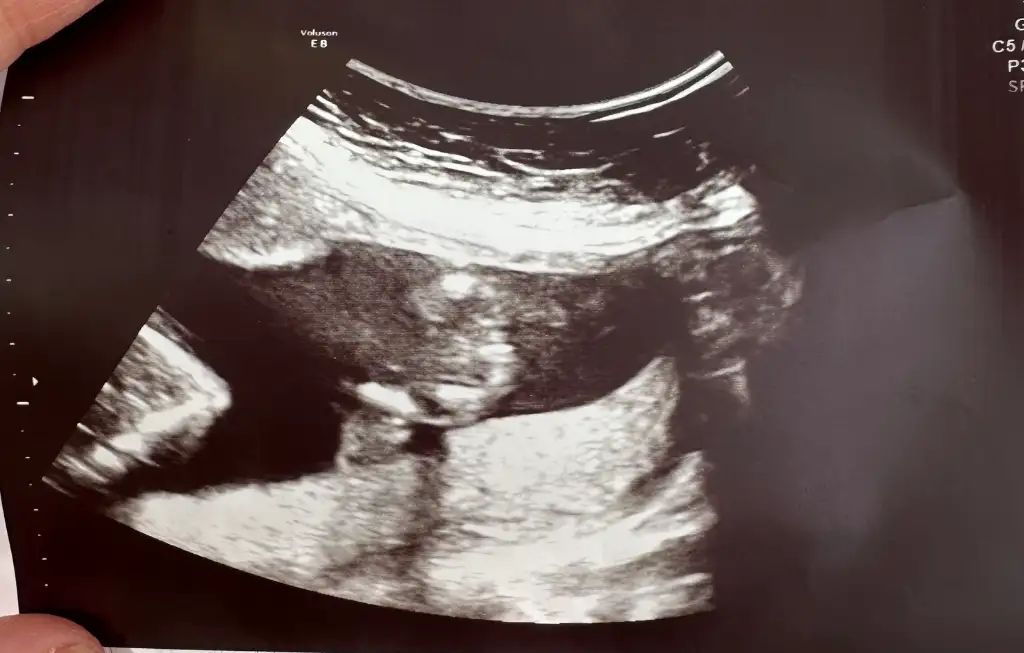

İyi günler. Bacak arası görüntüden tahmin ede bilirmisiniz acaba?Evet burdaki tahmin ettigim bi kaç kişi vardı yazsınlar dogru ettiklerim